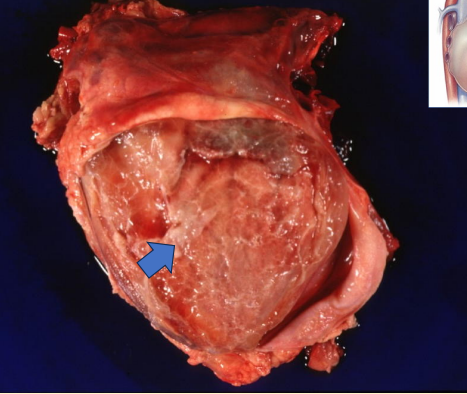

What is the blue arrow pointing to?

fibrin strings

What condition does this image show?

porcine heart with strep suis

What happens to the pig’s heart when it has strep suis?

fibrin polymerise from fibrinogen, coats tissue surfaces, can be degraded